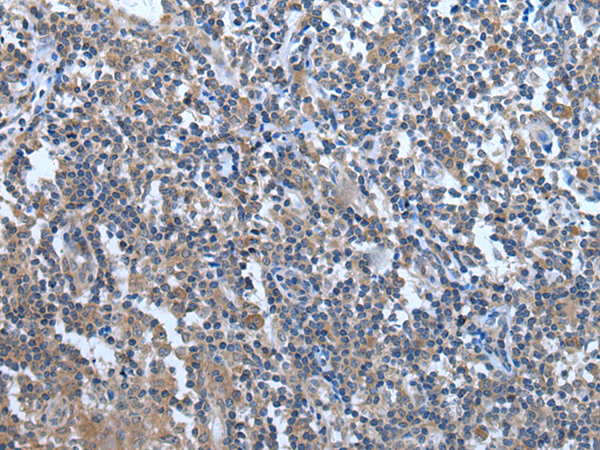

分类: 科研抗体货号: P12859别名: YB1; BP-8; CSDB; DBPB; YB-1; CBF-A; CSDA2; EFI-A; NSEP1; NSEP-1; MDR-NF1应用: IHC反应种属: Human, Mouse, Rat